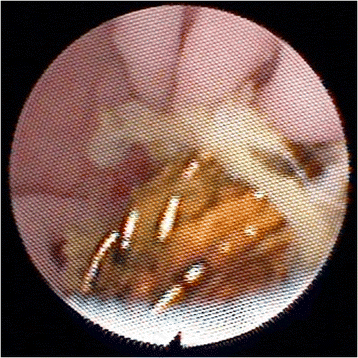

Thus, approximately 10 months after his BD reconstruction, he was admitted electively for percutaneous transhepatic cholangiography (PTC) and balloon dilatation of this bilio-enteric anastomosis. After confirmation of the stricture by PTC, a 4 French catheter was inserted into his left ductal system and an 8.5 French pigtail catheter was placed into his right ductal system but neither could be advanced into the enteric limb (Figure 3). Two further attempts were made at PTC balloon dilatation, but both failed. It was decided to attempt to visualise the anastomosis through the Terblanche access limb. Choledochoscopy through the modified Terblanche access limb showed multiple radiological coils from the previous embolisation of the RHA pseudoaneurysm at the site of the anastomoses, causing a mechanical obstruction (Figure 4, Figure 5). Laparotomy was performed and the bilio-enteric anastomoses were taken down to remove the coils. The right and left ductal systems were evaluated with intraoperative cholangiogram and the bilio-enteric anastomoses were revised using the existing Roux limb around 10 French infant feeding catheters, which were externalised again through the modified Terblanche limb.